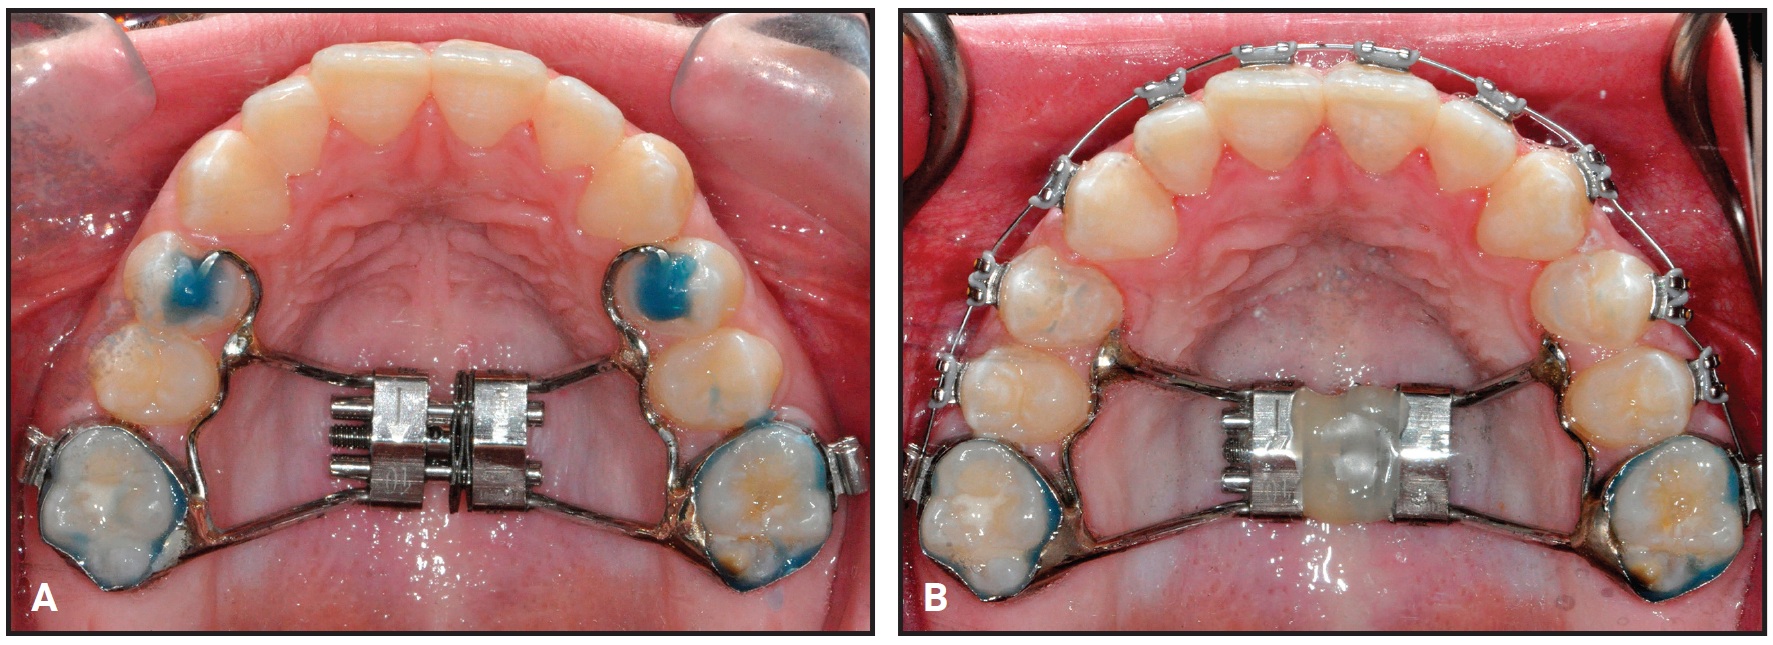

A nickel titanium Memoria Leaf Spring Activated Expander was placed and then reactivated 10 times at each monthly appointment until the correction was completed, in about two and a half months (Fig. 2).

Fig. 2 Case 1. A. Memoria Leaf Spring Activated Expander*** cemented in place. B. After two and a half months of expansion, expansion screw stabilized with flowable composite.

After intermolar expansion of 3.87mm had been obtained (Fig. 3, Table 1), flowable composite was placed in the expansion screw housing to stabilize the appliance. A maxillary impression was then obtained and digitized to evaluate the molar angulation changes (Fig. 4). Bony separation suggesting mild sutural disruption was indicated by radiolucency on the occlusal radiograph (Fig. 5).